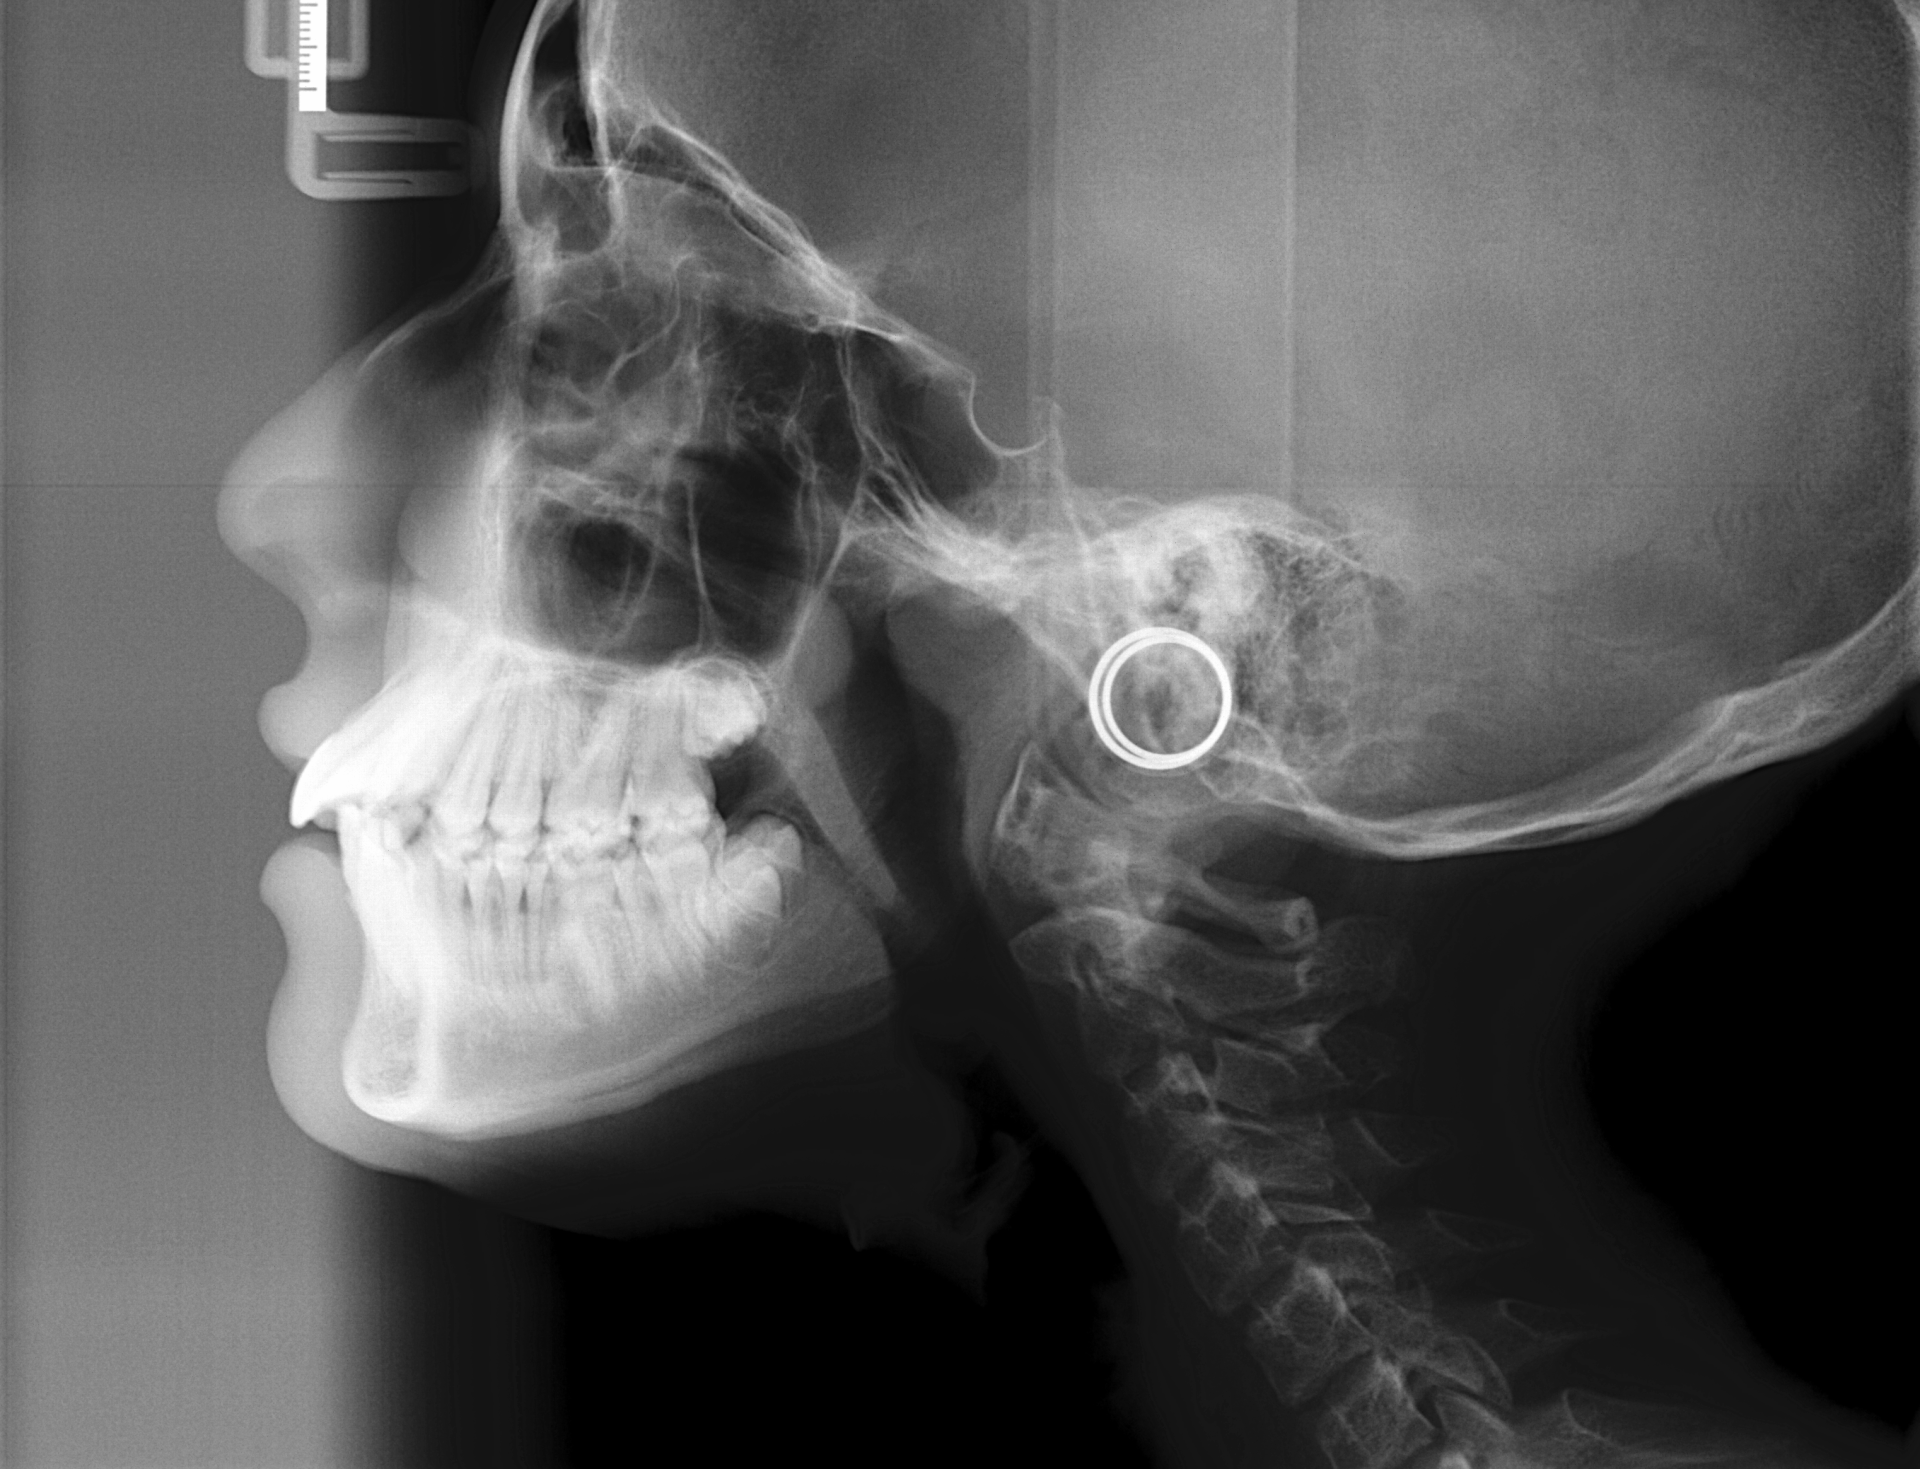

ORTOPANTOMOGRAFIAS: ( Rx Panorámica)

Son radiografías de las dos arcadas, boca completa, y ofrece una vision generalizada de todas las estructuras óseas, dentales y articulares. Estas pueden ser

frontales o

laterales.